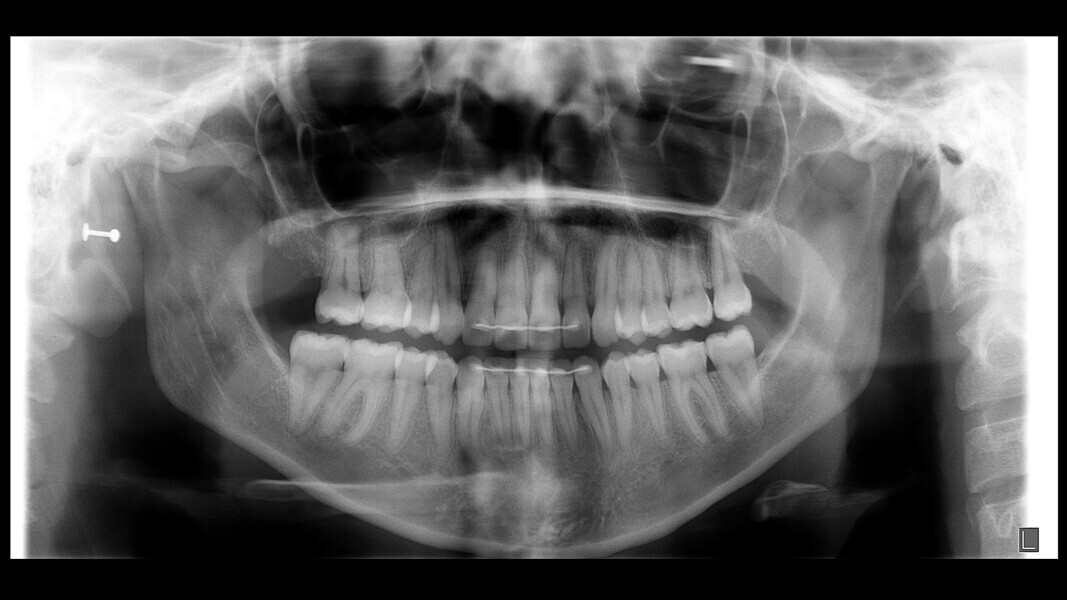

The 23-year-old dolichofacial female patient complained of not being able to chew properly. Facial examination showed a convex profile, an enlarged lower facial height, and a skeletal Class III malocclusion (Figs. 1–3). Intra-oral examination revealed an Angle Class III right subdivision malocclusion, anterior open bite, no overjet and a maxillary dental midline deviated about 3 mm to the right compared with the mandibular dental midline (Fig. 4). The panoramic radiograph confirmed previous extraction of the maxillary right first premolar and the presence of all four third molars (Figs. 5 & 6).